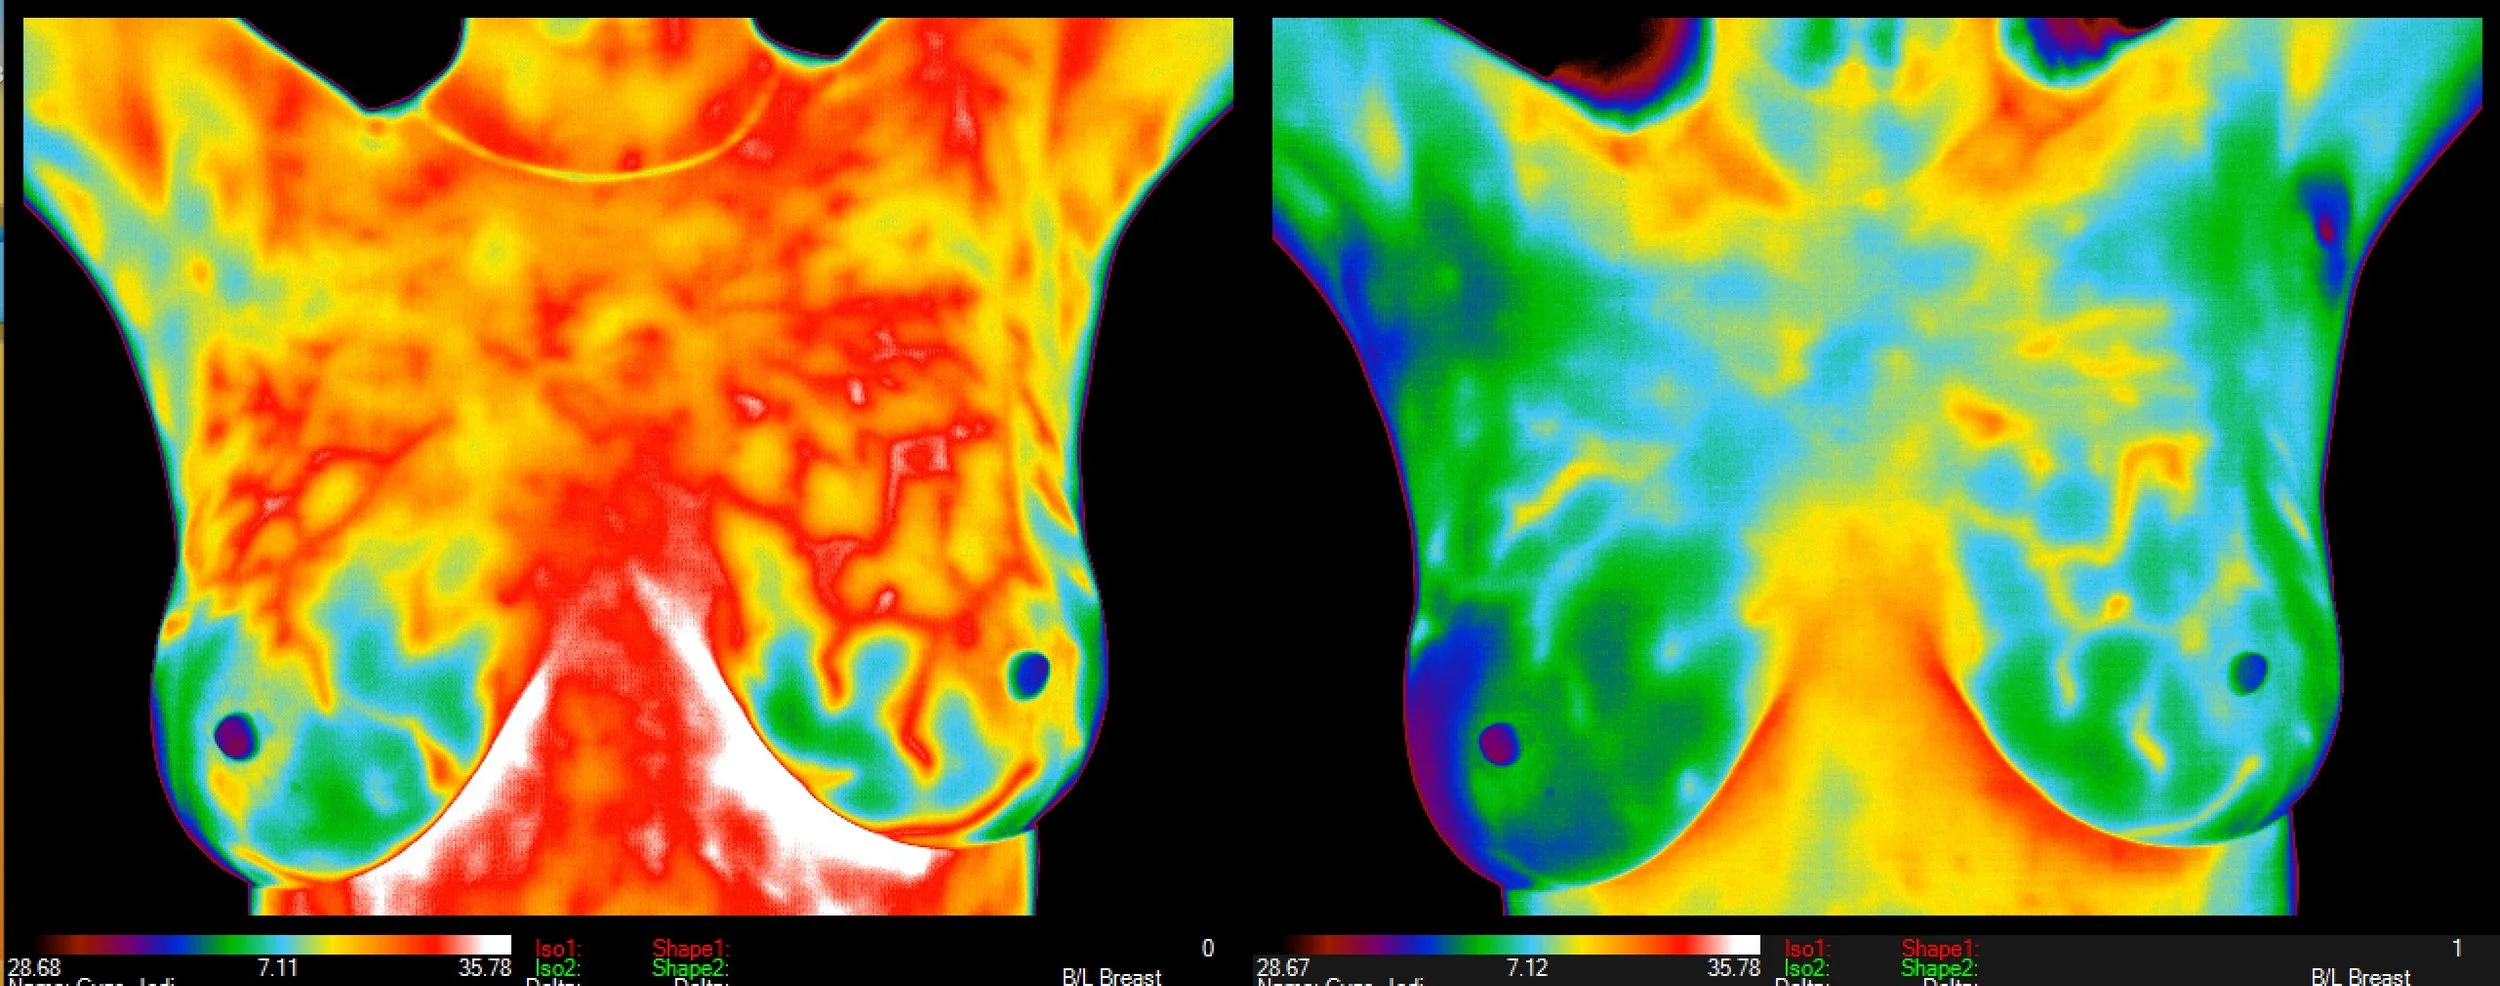

Below is the same woman, images are two years apart:

Her breast grades remained the same; however, we see “SIGNIFICANT IMPROVEMENT” in the pattern suggestive of unopposed estrogen (estrogen dominance or progesterone deficiency) that she was warned about by her breast imaging two years ago. She credits the improvement to intermittent fasting of 15-17 hours a day, said she read “fabulous book called Fast Like a Girl” that inspired her.

Please beware - usually fast-food thermography clinics do not or cannot identify the estrogen pattern let alone displaying it as standard on the report as quality thermography clinics do. Saying “thermography is good” is like saying “surgery is good” - it really depends on many factors. Skill of surgeon and technicians assisting, plus equipment quality all play a huge role in surgery as in thermography.